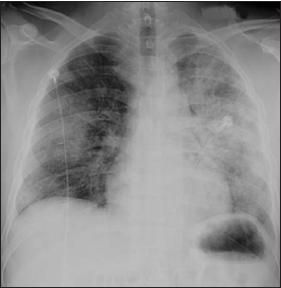

Laboratory test results revealed a normocytic anemia (hemoglobin, 5.8 g/dL; mean corpuscular volume, 91 fL) without eosinophilia, hyperkalemia (potassium, 6.0 mEq/L), and renal insufficiency (blood urea nitrogen, 96 mg/dL; creatinine, 13.6 mg/dL) with an active urinary sediment (protein more than 300 mg/d; red blood cells, 44 per high-power field). A chest radiograph showed diffuse bilateral patchy infiltrates (Figure 1), which were confirmed by a CT scan.

Figure 1 – Diffuse bilateral patchy infiltrates can be seen in this chest radiograph. The patient had presented with hemoptysis, fatigue, and dyspnea after an upper respiratory tract infection.